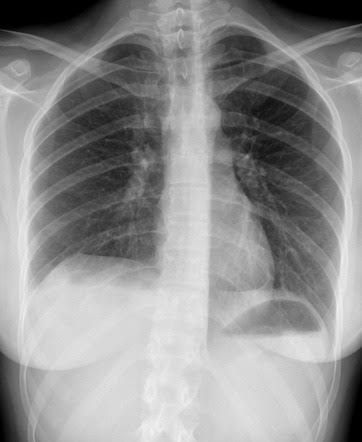

Westermark Sign

Westermark sign is a sign of pulmonary embolus seen on chest radiographs. It is one of several described signs of pulmonary embolus on chest radiographs.